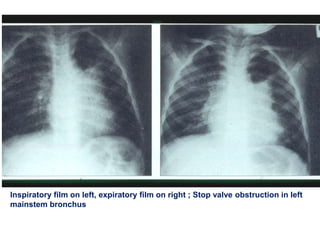

Inspiratory film on left, expiratory film on right ; Stop valve obstruction in left

mainstem bronchus

Chest X-ray forAspirated Foreign Bodies ƒ Foreign object radiopaque in 6 to 20 % ƒ CXR normal in 18 to 33 % ƒ CXR findings: –obstructive emphysema –atelectasis –pneumonia ƒ Expiratory film enhances CXR yield

Inspiratory film onleft, expiratory film on right ; Stop valve obstruction in left mainstem bronchus